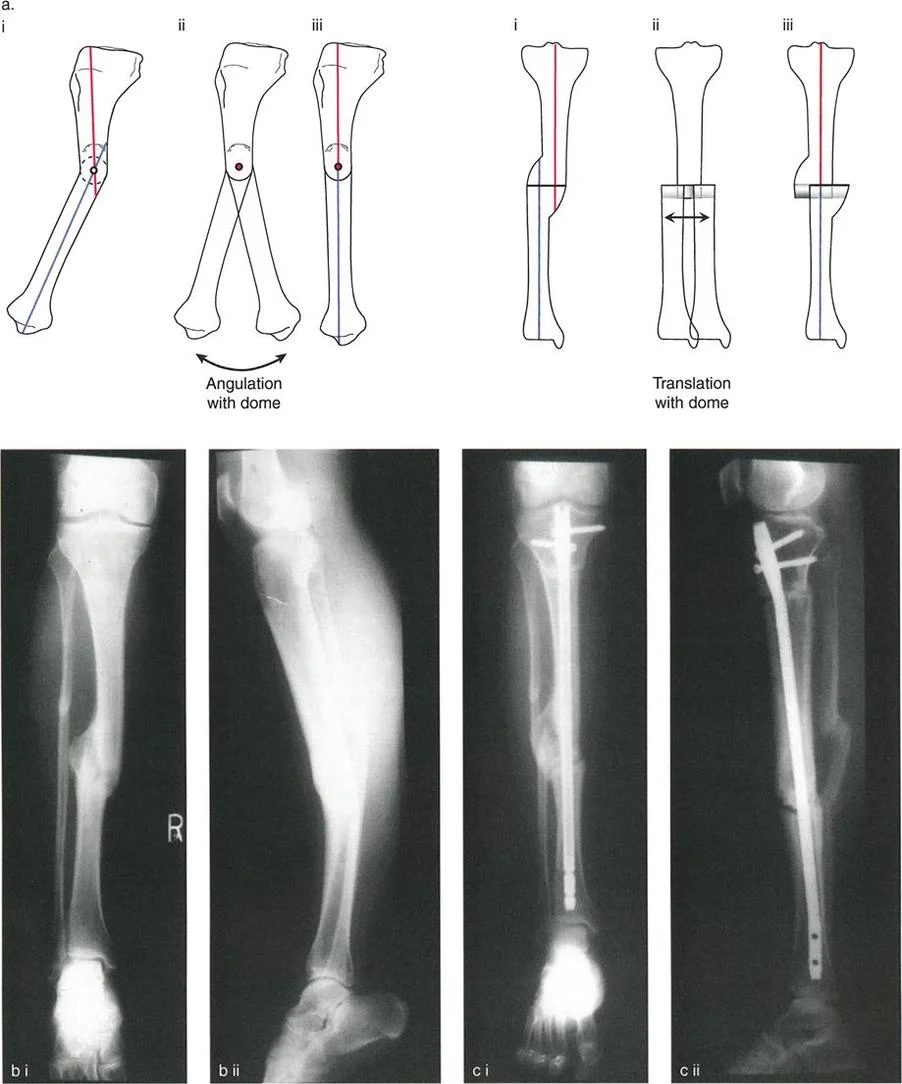

مبادئ تصحيح التشوهات الجراحية: فن قطع العظم

تعتبر عملية قطع العظم (Osteotomy) هي الإجراء الجراحي الأساسي لتصحيح تشوهات الأطراف. إنها ليست مجرد "قطع في العظم"، بل هي تعديل هندسي محسوب بدقة لإعادة المحاذاة الطبيعية للطرف مع احترام الحدود الفسيولوجية للأنسجة الرخوة المحيطة والأوعية الدموية والأعصاب وقدرة العظم على الشفاء.

ما هي عملية قطع العظم (Osteotomy)؟

قطع العظم هو إجراء جراحي يتم فيه قطع العظم وإعادة تشكيله أو إعادة محاذاته لتصحيح تشوه أو لتخفيف الضغط عن مفصل متآكل. يمكن أن تتضمن هذه العملية إزالة قطعة صغيرة من العظم (قطع إسفيني غالق) أو فتح فجوة وتثبيتها (قطع إسفيني فاتح).

قواعد بالي لقطع العظم

تُعد مبادئ الدكتور درور بالي (Dr. Dror Paley) حجر الزاوية في فهم سلوك العظام عند قطعها وتصحيحها. تبسط هذه القواعد المعقدة كيفية تفاعل أجزاء العظم عند التلاعب بها حول محور معين.

القاعدة الأولى: التصحيح المثالي للزاوية:

- عندما يتم إجراء قطع العظم ومحور التصحيح (النقطة التي يتم حولها ثني العظم) في نفس مستوى مركز دوران الزاوية (CORA)، يحدث تصحيح زاوي نقي.

- في هذه الحالة، تعود الخطوط الميكانيكية للجزء القريب والبعيد من العظم إلى محاذاة مثالية دون أي انزياح جانبي (إزاحة) ثانوي. هذا هو السيناريو المثالي للتشوهات البسيطة في منطقة الميتافيز (نهاية العظم القريبة من المفصل).

القاعدة الثانية: التصحيح الزاوي مع انزياح العظم:

- عندما يتم إجراء قطع العظم في مستوى مختلف عن مركز دوران الزاوية (CORA)، ولكن محور التصحيح يظل في الـ CORA، فإن الخطوط الميكانيكية للطرف ستعود إلى محاذاة مثالية.

- ومع ذلك، ستخضع نهايات العظم عند موقع قطع العظم لانزياح جانبي (ترجمة) بالإضافة إلى التصحيح الزاوي. هذا ما يُعرف بعملية "قطع العظم الزاوي-الترجمي" (Angulation-Translation - a-t Osteotomy).

القاعدة الثالثة: انزياح ثانوي غير مرغوب فيه:

- عندما يتم إجراء قطع العظم ومحور التصحيح كلاهما في مستوى مختلف عن مركز دوران الزاوية (CORA)، سيحدث انزياح جانبي ثانوي غير مرغوب فيه.

- في هذه الحالة، ستبقى الخطوط الميكانيكية متوازية ولكنها لن تكون متطابقة، مما يؤدي إلى استمرار انحراف المحور الميكانيكي (MAD) على الرغم من تصحيح التشوه الزاوي الظاهري. هذا الوضع غير مرغوب فيه ويجب تجنبه.

عملية قطع العظم الزاوي-الترجمي (a-t osteotomy) هي تطبيق سريري للقاعدة الثانية لبالي، حيث يتم إزاحة أجزاء العظم عمدًا لتحقيق محاذاة مثالية للمحور الميكانيكي.

قطع العظم الإسفيني الفاتح مقابل الإسفيني الغالق

يُعد قرار استخدام قطع العظم الإسفيني الفاتح أو الغالق خطوة حاسمة قبل الجراحة، ويتأثر بشدة بحجم التشوه، وموقع الهياكل العصبية الوعائية، وطول الطرف المطلوب.

التصحيح الفوري (Acute Correction):

- مناسب لكل من التثبيت الداخلي (الصفائح، المسامير النخاعية) والتثبيت الخارجي.

- فعال للغاية، حيث يسمح بإجراء العملية على مرحلة واحدة، ولكنه محدود بمدى تحمل الأنسجة الرخوة للتمدد المفاجئ.

- إذا تم استخدام المنشار لقطع إسفيني فاتح، فيجب توخي الدقة الفائقة. الري المستمر بمحلول ملحي مبرد إلزامي لمنع النخر الحراري (الحرق) لأطراف العظم، والذي من شأنه أن يعرض الشفاء للخطر بشدة ويؤدي إلى عدم الالتئام.

- يمكن أن يكون التصحيح الفوري دقيقًا للغاية، خاصة عند استخدام تقنيات التثبيت بالصفائح بمساعدة المثبت الخارجي (Fixator-Assisted Plating - FAP) أو التثبيت بالمسامير النخاعية بمساعدة المثبت الخارجي (Fixator-Assisted Nailing - FAN). في هذه التقنيات، يُستخدم مثبت خارجي مؤقت لضبط التصحيح المثالي، وتعديل الانزياح، وتثبيت المحور الميكانيكي قبل تطبيق الأجهزة الداخلية بشكل دائم.